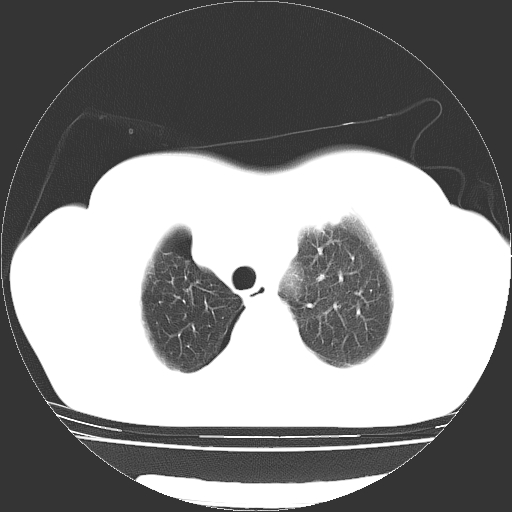

以下是引用zhangzhongshou在2008-3-22 12:52:00的发言:[br]1、右侧液气胸。[br]2、腹水。建议进一步检查。

以下是引用鲁巨ct在2008-3-22 14:10:00的发言:[br]1、右侧液气胸,右中下叶节段性不张。[br]2、腹水,建议上腹部ct检查

以下是引用zjzjr在2008-3-22 17:19:00的发言:[br]1、右侧液气胸,右下叶节段性不张。[br]2、腹水,建议上腹部ct检查